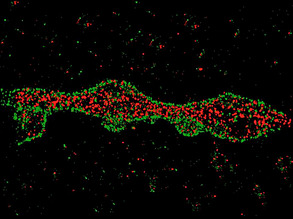

Watching Wounds